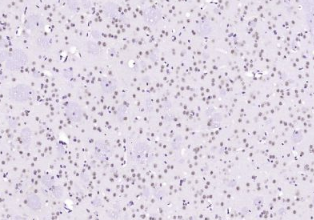

​多聚甲醛固定,石蜡包埋(小鼠脑组织);用柠檬酸钠缓冲液(pH6.0)煮沸15min后获得抗原;用3%过氧化氢阻断内源性过氧化物酶20分钟;在37℃下封闭缓冲液(正常山羊血清)30min;用(Alpha B Crystallin)多克隆抗体进行抗体孵育。在4°C下1:400整晚,然后根据SP试剂盒(兔子)说明和DAB染色进行操作。